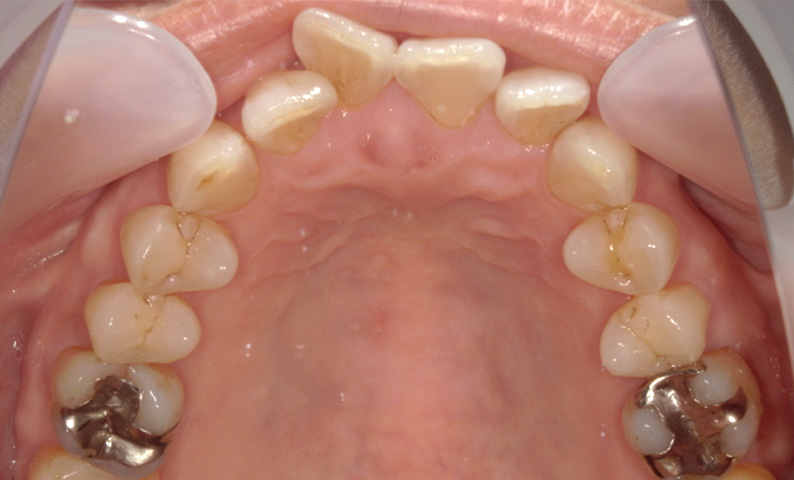

症例_001 「出っ歯」症例

治療期間:13ヶ月金額:54万円+税20代女性出っ歯捻転歯

| Before | After |

|---|---|

|